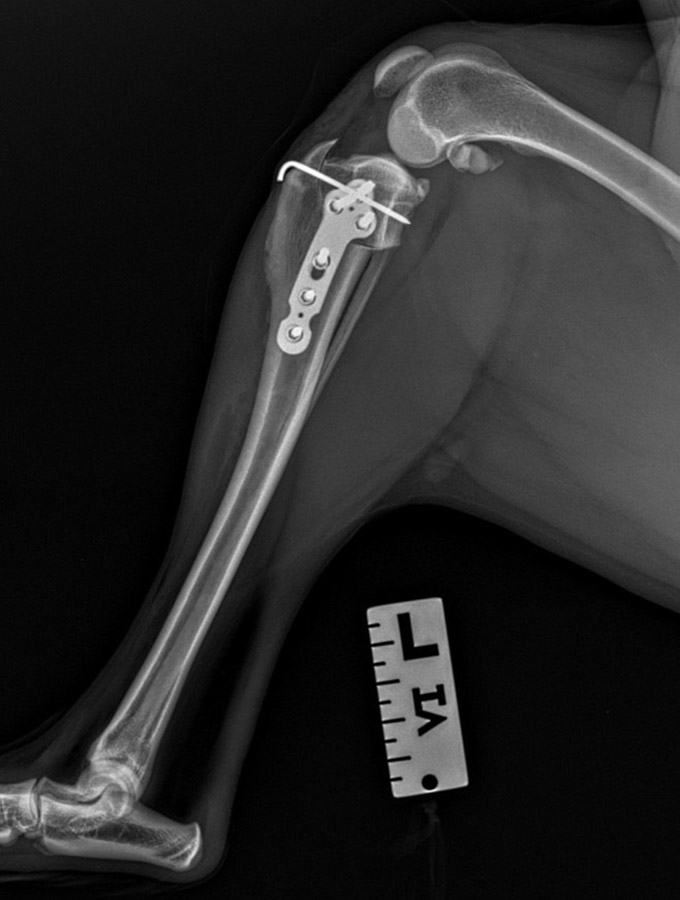

1. TPLO (Tibial Plateau Leveling Osteotomy), CCWO (Cranial Closing Wedge Osteotomy) i CBLO (CORA Based Leveling Osteotomy) – Zabiegi polegające na zmianie kąta powierzchni stawu piszczelowego przez wykonanie osteotomii.

2. TTA (Tibial Tuberosity Advancement), TTA Rapid oraz MTTA – Osteotomia, która polega na przesunięciu guzowatości kości piszczelowej, co zmienia biomechanikę sił działających na staw kolanowy.